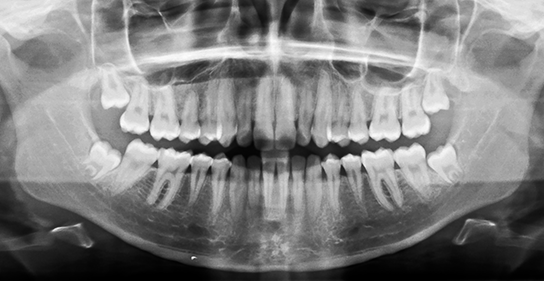

検査診断矯正相談以上の詳しいお話をご希望なさった場合は、具体的な治療方針を考えます。そのためにレントゲン、口腔内写真、口腔模型などの検査を行います。